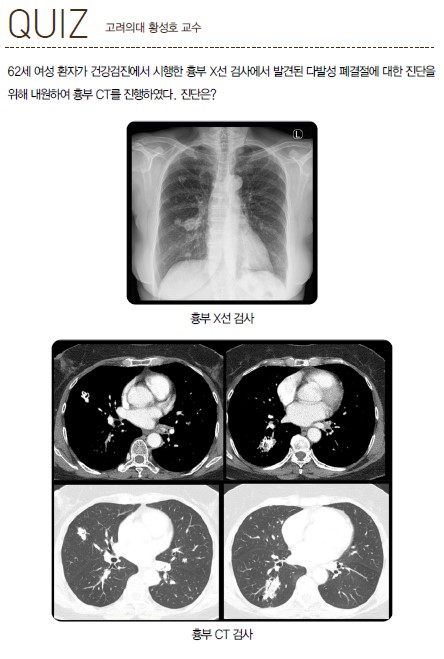

퀴즈